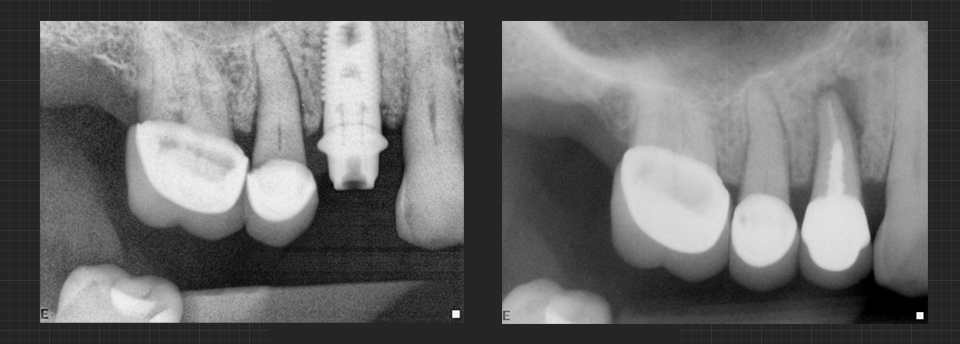

Missing teeth can be a nuisance, both cosmetically and functionally; you may feel self-conscious about a gap in your smile, and that gap will almost certainly cause problems with biting and chewing. While there are several procedures dentists use to fill in gaps left by missing teeth, dental implants are by far the most natural-seeming in form and function. A dental implant is nearly indistinguishable from a natural tooth and can last a lifetime with proper maintenance. Click here to find out more.